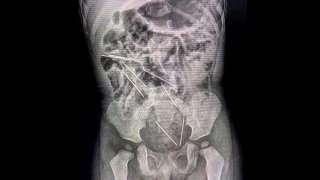

มีเด็กต้องระวัง!! 2 ขวบ"กลืนเข็ม 8 เล่ม"ลงท้อง

เด็กชายรายนี้ถูกนำตัวส่งโรงพยาบาลท้องถิ่นในจังหวัดลา ลิเบรตาด ทางตอนเหนือของเปรู หลังจากพ่อแม่สังเกตเห็นว่าเขาไม่รู้สึกตัวและมีอาการท้องเสีย แพทย์ได้ทำการเอ็กซเรย์และพบว่ามีหัวเข็มฉีดยาติดอยู่ในกระเพาะอาหารและลำไส้ ทีมแพทย์ได้ตัดสินใจทำการผ่าตัดฉุกเฉินเป็นเวลานานกว่า 2 ชั่วโมง เพื่อนำหัวเข็มฉีดยาทั้งหมดออก การผ่าตัดประสบความสำเร็จและเด็กชายปลอดภัยดี แพทย์สันนิษฐานว่าเด็กชายน่าจะกลืนหัวเข็มฉีดยาเข.. ดูเพิ่ม